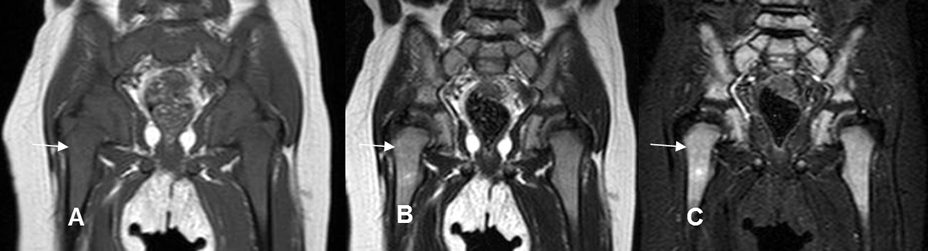

Fig 4 A. Medula ósea normal de un niño.

A: RM coronal en T1, B: RM coronal en T2 y C: RM coronal en STIR. Apariencia de la medula ósea en un niño, la cual es hipointensa en T1 e hiperintensa en T2 y STIR, por predominio el de la medula roja.

Fig 4 B. Medula ósea en niño normal

A: RM coronal en T1 y B: RM coronal en STIR. Reconversión, con presencia de medula ósea grasa, en la epífisis distal del fémur y proximal de la tibia y roja en ambas metafisis.